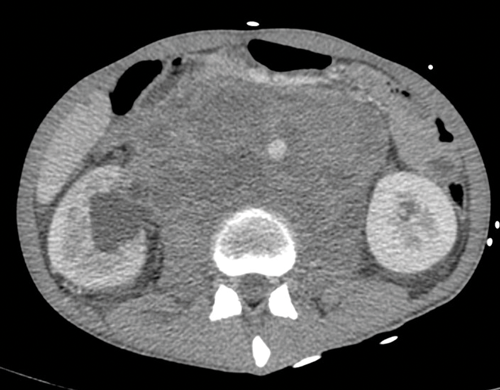

Figure 5. Massive retroperitoneal lymphadenopathy causing effacement of

the IVC, anterior displacement of the aorta and right hydronephrosis.

Nodes may be massive and encase renal vessels, displacing the aorta or inferior vena cava (IVC) and this is important when reporting the staging CT (Figure 5). Coronal views can be very useful to demonstrate the overall length of nodal disease as sometimes, on axial imaging the size of the nodes can be underestimated (Figure 6). Teratoma nodes may contain some areas of calcification or low attenuation areas of necrosis, which are less often seen in seminoma lymph nodes. Retroperitoneal lymph nodes often respond very well to chemotherapy agents, but teratoma nodes may require retroperitoneal lymph node dissection if they do not respond or there remains a sizable node at the end of the treatment.